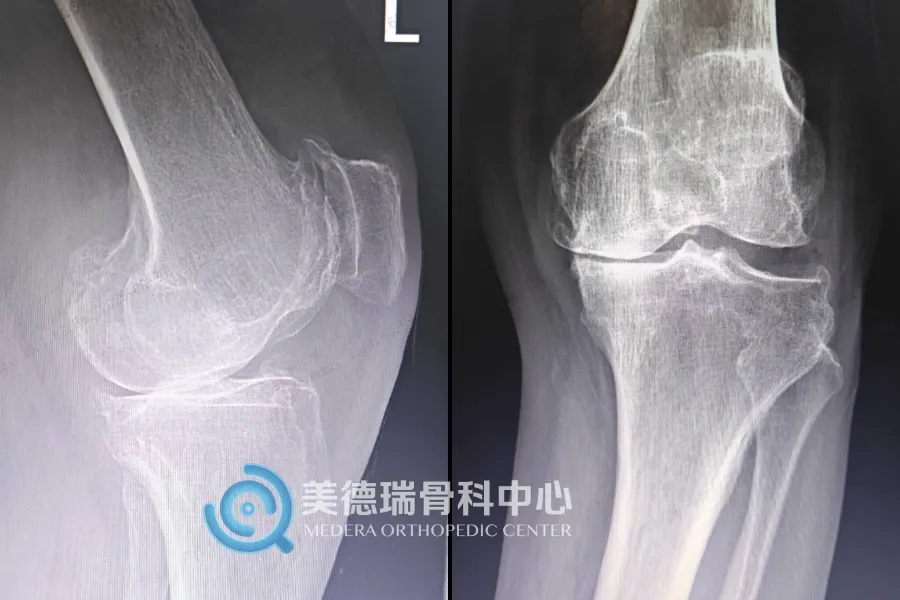

美德瑞关节脊柱中心主任及学科带头人吴厦医生对患者进行了全面评估,明确诊断为双膝重度骨关节炎。考虑到患者目前左膝疼痛更为严重,而全膝关节置换术本身存在创伤与康复周期,中心团队决定先为患者实施左侧全膝关节置换术,为后续整体康复奠定基础。